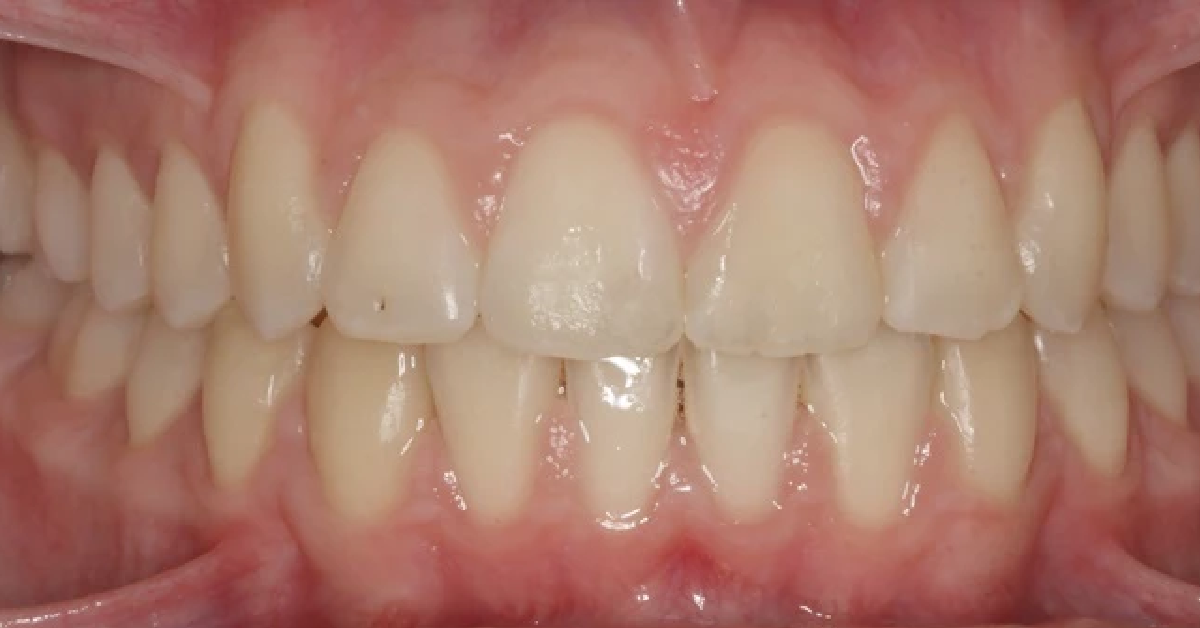

Vårt arbeid

Alle pasienter som vises har gitt skriftlig samtykke til at bildene kan brukes på klinikkens nettside.

Ønsker du en vurdering av behov for tannregulering, kan du ta kontakt med klinikken for time til konsultasjon.